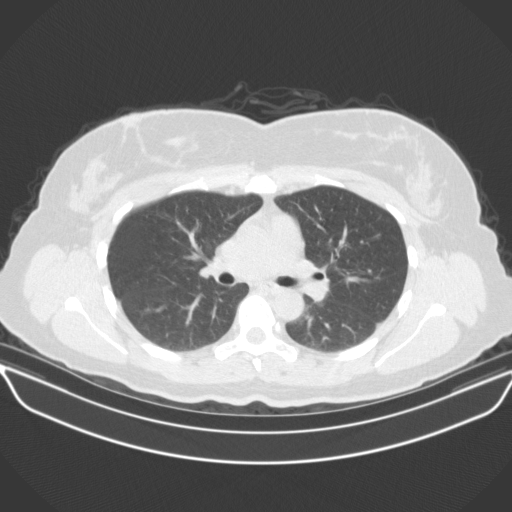

Original NATIVE CT scan (input)

No window - Raw intensity values

Lung window (WL -600, WW 1500 β†’ Low βˆ’1350, High +150)

Targeted Slice 70 - Lung Window Analysis (Generated vs Real Venous)

0.763

Lung SSIM

85.0

Lung RMSE

36.7

Lung MAE

Average Lung Window Metrics Across All Slices (170 slices) - Generated vs Real Venous

0.767

Lung SSIM (Avg)

89.5

Lung RMSE (Avg)

37.4

Lung MAE (Avg)